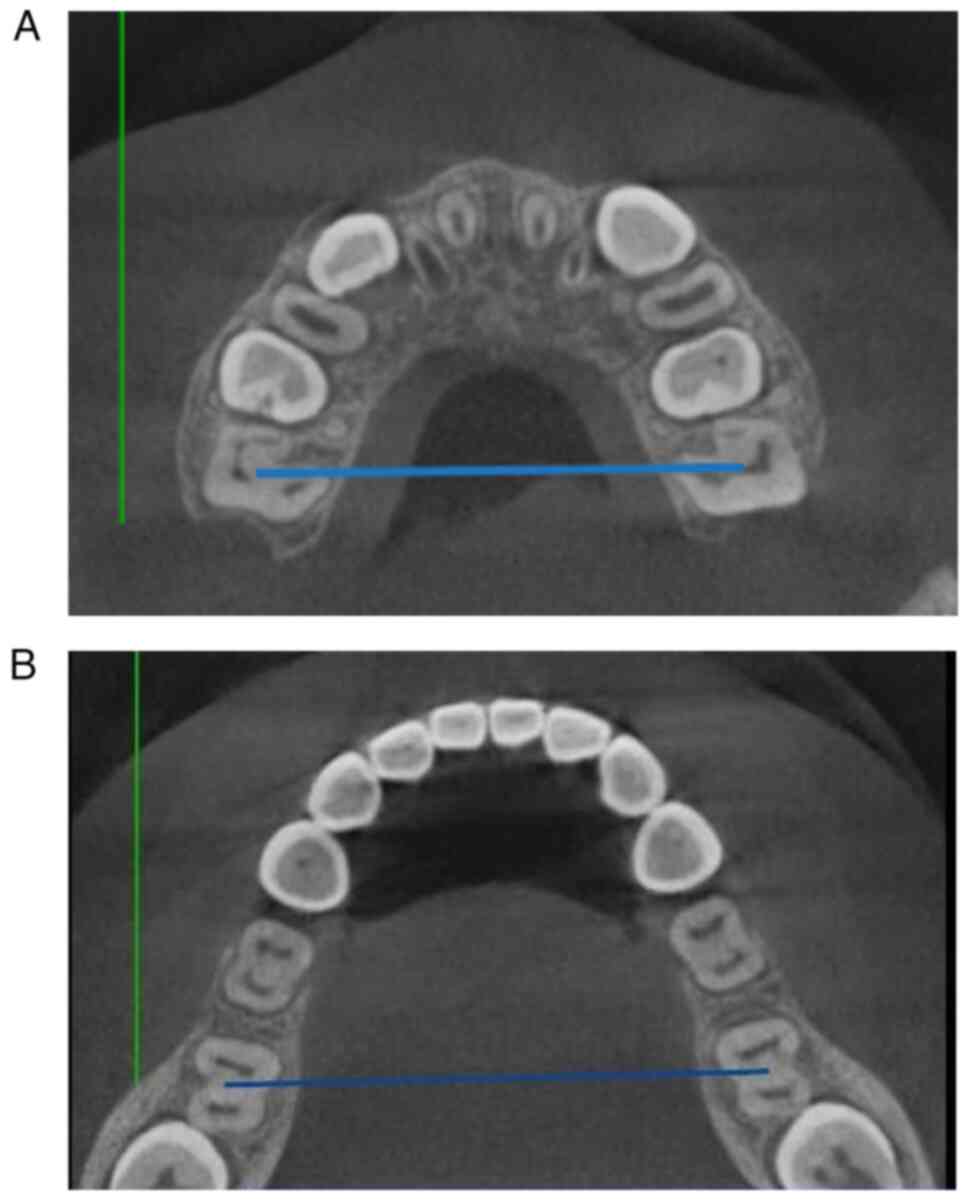

As previously described (25), lateral cephalograms and CBCT were taken before the treatment to examine the sagittal and transverse imbalance of the upper and lower jaw. CBCT was used to measure the width of each patient's maxillary and mandibular basal bone arches (the width of the connection between the root furcations of the bilateral first molars) prior to treatment (Fig. 1A and B, respectively) (26). Rapid maxillary expansion was first used for each patient included in the study (Fig. 2) with an occlusal pad for maxillary rapid expansion. The coil spring was required to be opened 0.5 mm (2 revolutions/day) daily. The width of the upper and lower jaws was adjusted to make the width of the maxillary base bone arch 2 mm larger than that of the mandibular base bone arch. After completing the maxillary expansion, the Petit-type facemask (Hangzhou West Lake Biological Material Co., Ltd.) (Fig. 3) was implemented with a force of 450 g on each side at an angle of 20-30° downward to the maxillary plane. Traction lasted for 14 h per day (27). Lateral cephalograms were taken after about one year of traction.

Figure 1

(A) Example of the pre-treatment CBCT measurement of the width of maxillary basal bone arches; (B) Pre-treatment CBCT measurement of the width of mandibular basal bone arches. CBCT, cone beam computed tomography.